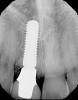

Plugging into digital workflows provides opportunities to integrate CAD/CAM technologies at every step of the treatment process for dental implants. In another example, a patient presented with a failing tooth No. 8 (Figure 6 and Figure 7). After discussing treatment options, the patient chose to forgo any treatment to address tooth and soft-tissue asymmetries and wanted to proceed with a dental implant-supported restoration without additional treatment. After integrated 3-dimensional planning, the tooth was extracted, and then an implant and the final custom CAD/CAM abutment (titanium base with zirconia supra-structure) were placed with a provisional restoration in the same visit (Figure 8 and Figure 9). Soft-tissue grafting was also done at the same visit to address the deficient buccal tissue height on No. 8 (Figure 10). At 3 months, the patient presented for the final restoration, with excellent healing around the implant (Figure 11) and soft-tissue healing guided by the custom abutment (Figure 12).

Fig 11. Radiograph of healed implant site No. 8 at 3 months.

Figure 11